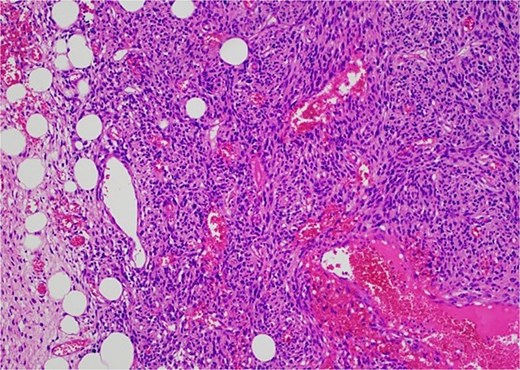

Histology revealed a multilobulated spindle cell lesion, with low- and high-grade areas, with an abrupt transition between these areas. There was an adjacent focus of adipose tissue with rare cytologic atypia suggestive of possible WDL, which indicated that the tumor mass may represent DDL. However, there was a single focus of lipoblasts identified, bringing up the differential of pleomorphic liposarcoma. Therefore, in situ hybridisation was performed and showed MDM2 amplification, which confirmed the diagnosis of DDL, with likely homologous lipoblastic morphology. The tumour was excised with clear margins (Figs 3–8).

Low-grade component with abrupt transition to high-grade component (asterisk).